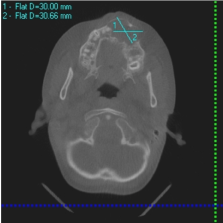

A healthy 12-year-old male was referred from orthodontic clinic to the maxillofacial clinic of the faculty of dentistry of Cairo University (Egypt) for treatment of a large periapical lesion around the left maxillary central incisor. Orthopantomography (Figure 1) revealed a large periapical radiolucency, about 3 cm in the horizontal plane and 3 cm in the vertical plane, associated with teeth 21, 22, 23, 24 and possibly 25 and losing in central incisors. Clinical examination revealed labial swelling over these teeth, and facial asymmetry, and the area was tender to palpation and percussion. Teeth 22, 23 and 24 did not respond to thermal and electrical pulp tests. The provisional diagnosis was radicular cyst. Computed tomography (CT) revealed a lesion about 3 cm wide in the anteroposterior plane affecting the entire right premaxilla and contacting the floor of the nose and the maxillary sinus (Figure 2). Swelling, a buccal cortical break and expansion of the bone were obvious; these features indicated that the lesion was benign.

Figure 2. Computed tomography (CT) revealed a lesion in the anteroposterior plane affecting the entire right premaxilla.